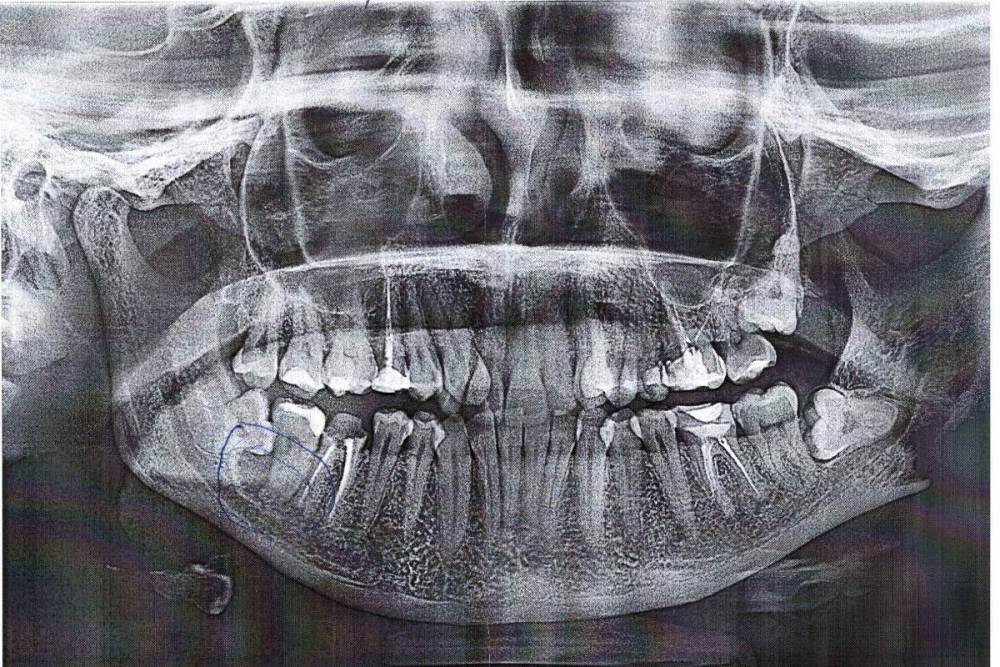

Джастина Опубликовано 4 декабря, 2023 Поделиться Опубликовано 4 декабря, 2023 Здравствуйте! Подскажите, пожалуйста, есть ли на снимке киста? Ссылка на комментарий

Джастина Опубликовано 4 декабря, 2023 Автор Поделиться Опубликовано 4 декабря, 2023 В том то и дело, что НИЧЕГО! Я пришла к стоматологу, узнать можно ли поставить коронку на зуб. Врач зуб осмотрел, сказал - зуб твердый, идите на снимок. Мне по ошибки сделали панорамный снимок, вместо точечного, по результатам которого врач-ортопед, сказал, что сначала надо кисту удалить вместо с 8-ой, а то вдруг при удалении кисты я лишусь сразу трех зубов, поэтому нет смысла сейчас начинать коронкой заниматься. Ссылка на комментарий

Irouil Опубликовано 5 декабря, 2023 Поделиться Опубликовано 5 декабря, 2023 Я рекомендую сделать компьютерную томограмму (КЛКТ), она может дать значительно более точную картину Вероятнее всего значительных рисков для 6-го зуба нет, а вот для 7-го зуба - вполне возможно. Диструкция - это разрушение костной ткани Ссылка на комментарий

Irouil Опубликовано 5 декабря, 2023 Поделиться Опубликовано 5 декабря, 2023 (изменено) @Джастина если там действительно очаг разрушения костной ткани подобных (с зуб) размеров - то это буквально дырка в челюсти, которая может вызвать её патологический перелом (то есть не от удара боксёра, а от пощёчины ребенка), потерю 7-го зуба, при дальнейшем разрастании - вовлечение нижнелуночкового сосудисто-нервного пучка и рисками онемения и провисания половины нижней губы в долгосрочной перспективе. И это я ещё молчу про самые грозные осложнения Изменено 5 декабря, 2023 пользователем Irouil Ссылка на комментарий